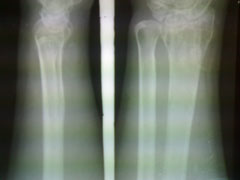

以下是引用杀毒软件在2009-7-17 11:54:00的发言:[br]骨软化症,内分泌性骨病,大骨节病均不能排除,请结合实验室检查。

以下是引用随光逐影在2009-7-17 15:12:00的发言:[br]甲状旁腺机能亢进引起多发性纤维囊性骨炎?

以下是引用zxl51642在2009-7-17 10:13:00的发言:[br]多关节骨质疏松并关节间隙狭窄,关节变形。考虑类风湿,结合病史及实验室检查(rf因子)。[br]

以下是引用dr.king在2009-7-18 20:57:00的发言:[br]甲状旁腺机能亢进引起多发性纤维囊性骨炎?进一步结合实验室检查。